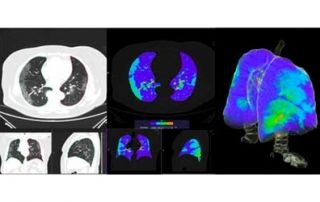

Detección y pronóstico a medio plazo en pacientes con Covid-19 mediante análisis automático de TAC de tórax y biomarcadores clínicos y analíticos

HT Médica (España)

En este proyecto se aborda el desarrollo de un sistema robusto, basado en modelos de aprendizaje profundo y big data, para la identificación, estratificación, y predicción del pronóstico de pacientes con Covid-19, a partir del análisis de una TC pulmonar y biomarcadores clínicos y analíticos […]